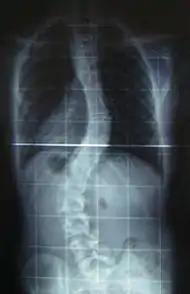

Scoliosis is a medical condition in which a person's spine has a sideways curve.[2] The curve is usually "S"- or "C"-shaped over three dimensions.[2][6] In some, the degree of curve is stable, while in others, it increases over time.[3] Mild scoliosis does not typically cause problems, but more severe cases can affect breathing and movement.[3][7] Pain is usually present in adults, and can worsen with age.[8]

When scoliosis is suspected, weight-bearing, full-spine AP/coronal (front-back view) and lateral/sagittal (side view) X-rays are usually taken to assess the scoliosis curves and the kyphosis and lordosis, as these can also be affected in individuals with scoliosis. Full-length standing spine X-rays are the standard method for evaluating the severity and progression of the scoliosis, and whether it is congenital or idiopathic in nature. In growing individuals, serial radiographs are obtained at 3- to 12-month intervals to follow curve progression, and, in some instances, MRI investigation is warranted to look at the spinal cord.[34]

The standard method for assessing the curvature quantitatively is measuring the Cobb angle, which is the angle between two lines, drawn perpendicular to the upper endplate of the uppermost vertebra involved and the lower endplate of the lowest vertebra involved. For people with two curves, Cobb angles are followed for both curves. In some people, lateral-bending X-rays are obtained to assess the flexibility of the curves or the primary and compensatory curves.

Scoliosis is defined as a three-dimensional deviation in the axis of a person's spine.[25][6] Most instances, including The Scoliosis Research Society, define scoliosis as a Cobb angle of more than 10° to the right or left as the examiner faces the person, i.e. in the coronal plane.[39]